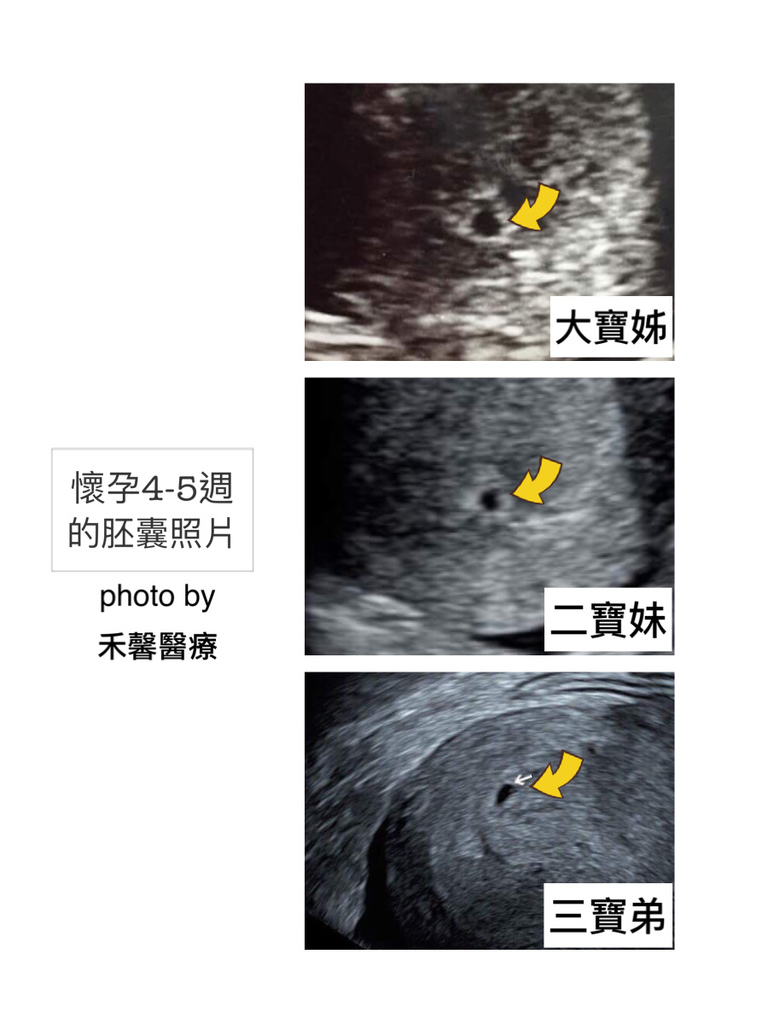

孕期 1 3個月baby每月成長記事 涼母與寶貝的生活 幸福是在點點滴滴中 痞客邦

心情故事 每個經歷都變成無價資產 懷孕初期第七週的變化 妞媽lisa Li X 妞爸169 分享愛

心情故事 每個經歷都變成無價資產 懷孕初期第七週的變化 妞媽lisa Li X 妞爸169 分享愛

心就在這裡停泊吧 藏了好久的祕密 肚子裡的小胎寶滿三個月了 孕4週 孕8週

心就在這裡停泊吧 藏了好久的祕密 肚子裡的小胎寶滿三個月了 孕4週 孕8週